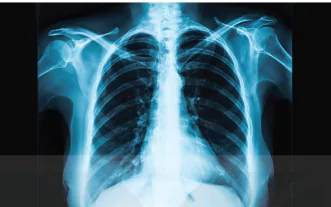

Trong chụp X-quang, các mô dày, đặc (ví dụ như xương) sẽ chặn hầu hết tia X, trong khi các mô mềm như mỡ hoặc cơ, chặn ít hơn. Các mô chặn nhiều tia X sẽ hiển thị dưới dạng vùng trắng trên nền đen. Các mô mềm chặn ít tia X hơn được hiển thị với màu xám. Với những khối u, mô thường dày và đặc hơn các mô xung quanh, vì vậy chúng có màu xám nhạt hơn. Các cơ quan chứa nhiều không khí (chẳng hạn như phổi) thường có màu đen (Hình 6.3).

Hình 6.3. Hình ảnh chụp X-quang phổi